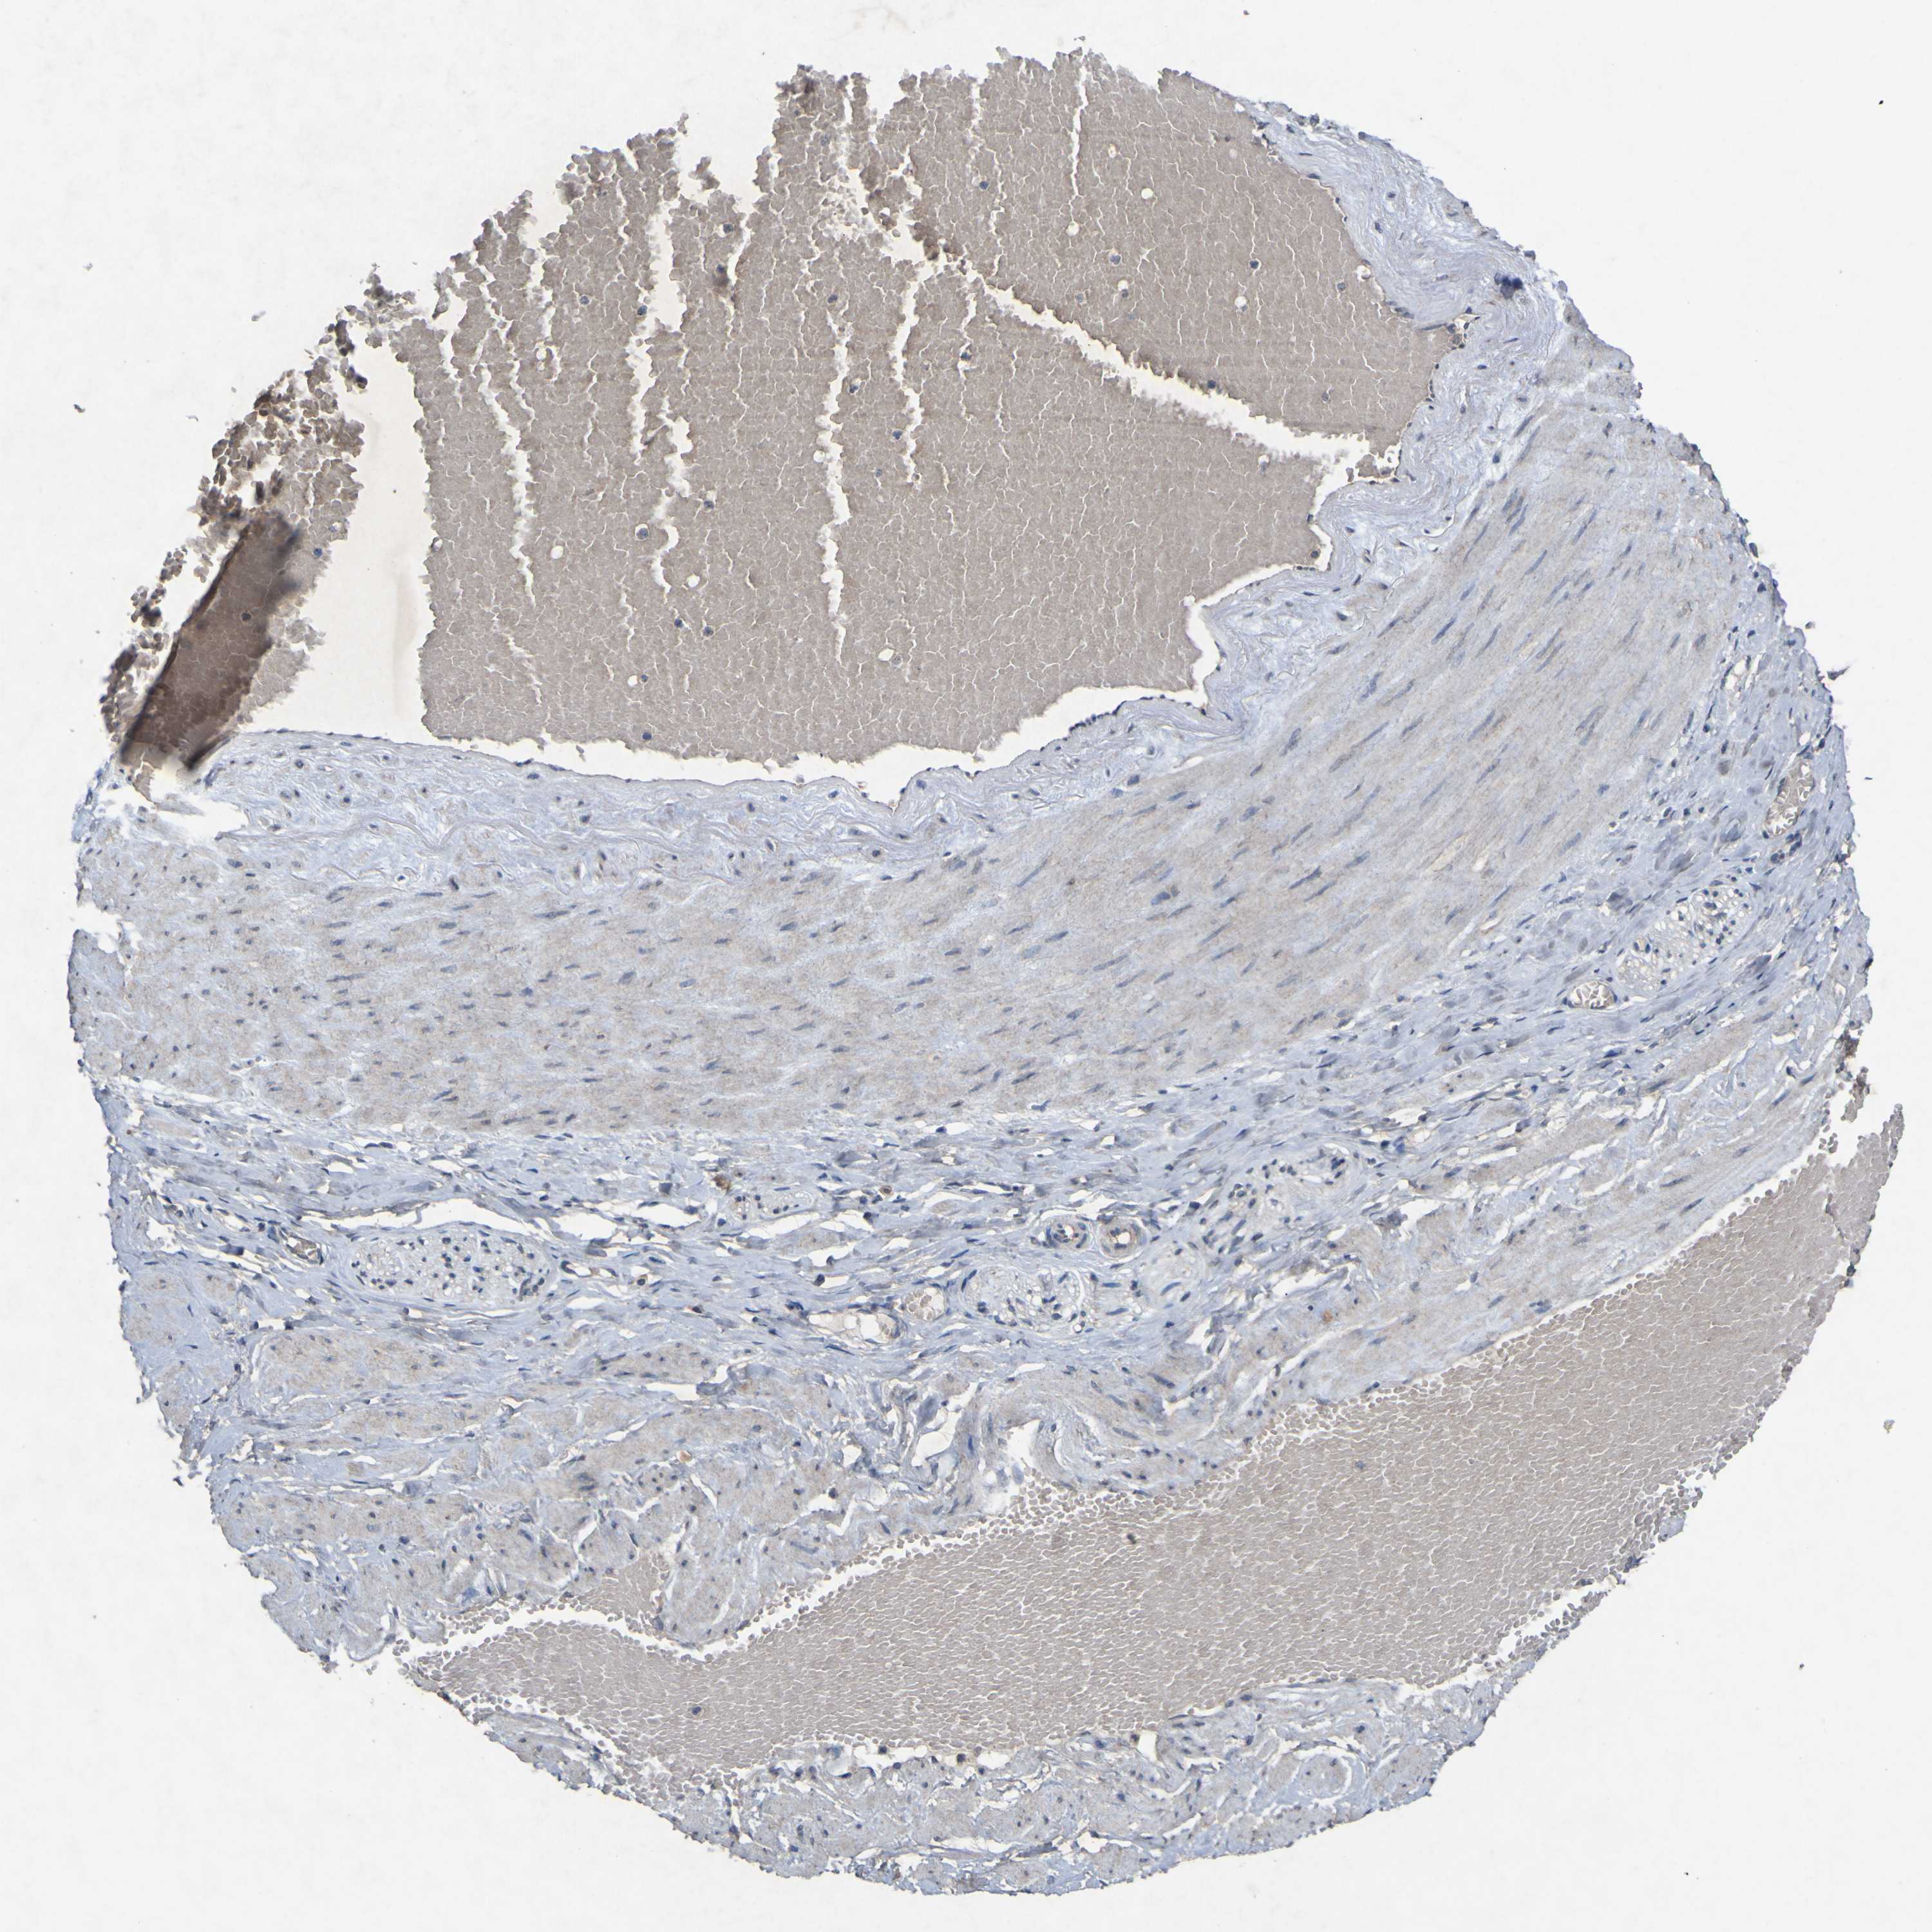

PRKCG